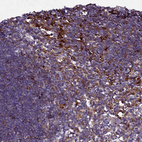

Immunohistochemical staining of human stomach shows positivity in glandular cells.